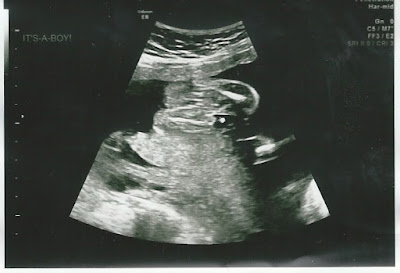

First things first. In case you didn't see the other post or get a text or hear it from me, we got our big ultrasound. And remember how we were so certain it was a girl? SO certain?

| See the little hand pointing? "It's a Boy!" |

You can probably guess that this caused a reaction. Actually, the ultrasound tech let it slip accidentally before we knew. She referred to "his head" and such a couple of times, but Mike and I didn't realize it, and we were joking about our 4-year-old insisting that it's a girl.

Then she caught herself and said, "Wait, do you know what it is yet? Do you want to?" To which we replied, "Yes, we want to know." "It's a boy."

At first I didn't realize she was serious, because she didn't say it very loudly or pronounced. So I was like, "Wait, are you serious?" She said, "Yep, it's a boy. That couldn't be anything else."